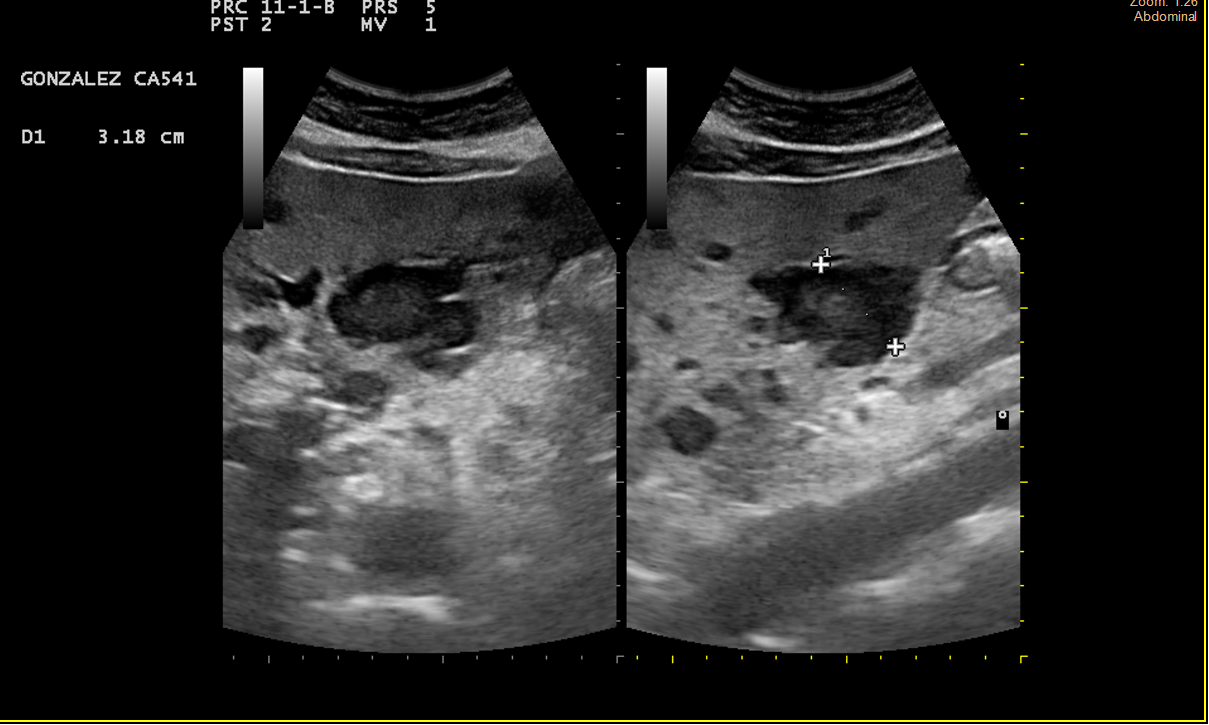

Alteración difusa de la ecoestructura hepática, presentando múltiples imágenes hipoecoicas, de diversos tamaños, resaltando una lesión en lóbulo hepático derecho de 3cm, tabicada y con ecos en su interior, con componente vascular asociado. Vesícula de aspecto normal.

TAC Abdominal: Hemangiomatosis hepática difusa sobre hepatopatía esteatósica.